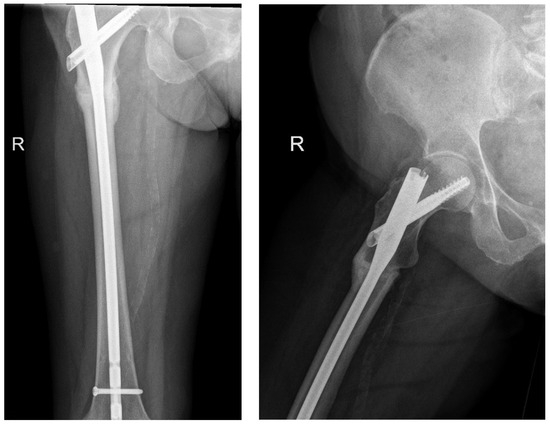

All 15 surgical procedures were followed up, 13 fractures had proven full radiological healing, and 2 of the atypical fractures did not heal from the time of surgery until their last follow-up assessment (Figure 5).

The following radiographs present the initial radiographs from the day of injury along with those obtained during the final OPD follow-up of the patient. The sequence presents radiographs demonstrating full radiological union (Scheme 1 and Scheme 2) and X-rays with no evidence of fracture healing at the final OPD follow-up (Scheme 3 and Scheme 4).

The two fractures that showed no evidence of radiological healing at the last follow-up were atypical subtrochanteric stress fractures of the femur (unicortical fractures). There may be a potential relationship between fracture healing and fracture patterns. However, because the study included only two cases of non-healed fractures, both of which were similar in type, it is challenging to draw definitive conclusions. Notably, one patient did not receive osteoporotic treatment following the incident, whereas the other patient was undergoing treatment with denosumab for osteoporosis. Although it cannot be conclusively stated that the fracture type influences healing, this observation warrants further investigation in future studies.

Scheme 4. X-ray of right femur AP view (left) and lateral view (right) of atypical subtrochanteric stress fracture—September 2024 (no features of healing).

Jcm 14 02858 sch004